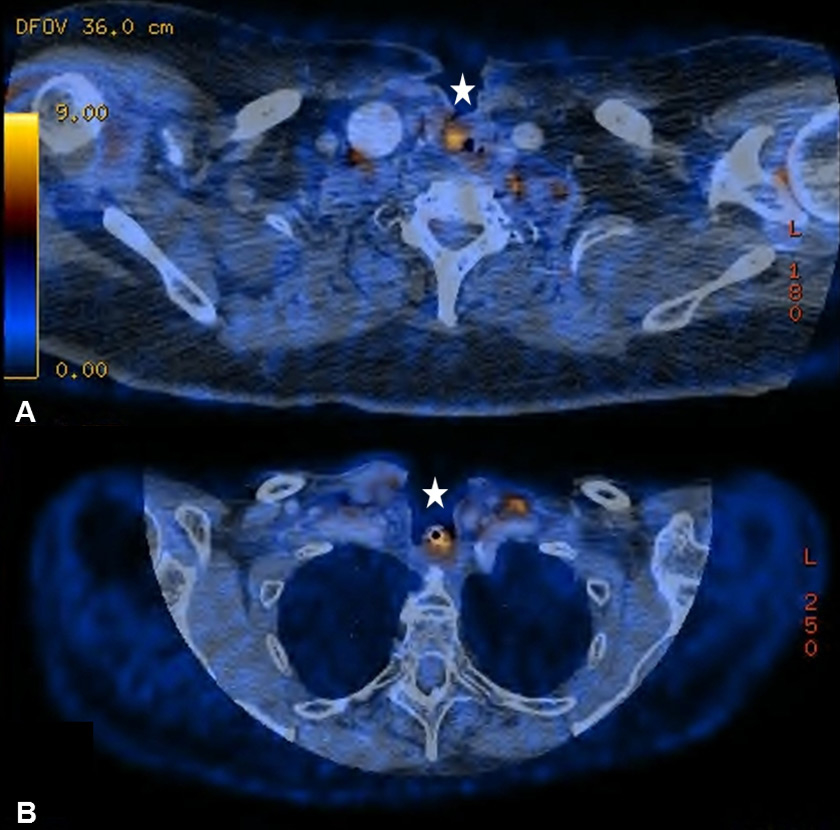

Figure 4

(A) Diffuse bilateral uptake in the thyroid without any morphological correlate in a 67-year old patient with no clinical, ultrasonographical or laboratory signs of thyroid dysfunction. (B) The same patient with corresponding probable reactive lymphadenopathy.

One of the most common causes of false-positive FDG findings in the post-treatment setting is increased FDG uptake due to benign conditions, such as inflammation, infections or granulomatous processes [27, 28]. Thus, literally any inflammatory process in the head and neck region can cause increased FDG activity [27]. In our study, 32.7% (52/179) of all FDG-positive lesions were categorised as inflammatory FDG uptake, of which a distinct attribution to an anatomical substrate or a treatment-modality was possible in only 44.2% (23/52). In 55.8% (29/52), FDG-positive findings were categorised as reactive, unspecific lesions; 15/29 of these lesions were related to cervical lymph nodes. Thereby, we often assumed multi-aetiological reasons of the FDG-positive lesion with treatment-related and non-treatment-related contributors [15]. Reactive lymphoid hyperplasia arising from inflammatory or infectious processes frequently causes FDG accumulation in cervical lymph nodes and often requires a clinical and ultrasonographic re-assessment [29]. However, in our case series invasive diagnostic procedures such as FNA were necessary in only two patients, indicating that those indistinct lesions in cervical lymph nodes are manageable in a reasonable way. Liu et al. investigated the clinical significance of diffuse thyroid uptake on PET-CT and usually considered FDG uptake into the thyroid to be benign and very likely secondary to thyroiditis and/or hypothyroidism [30] (fig. 4AB).